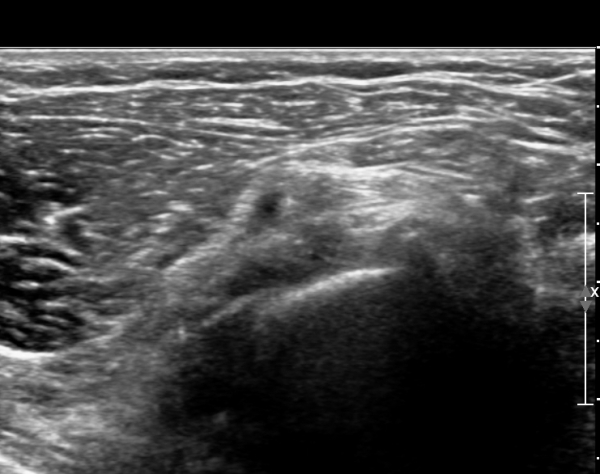

¾Æ·§ÆÈÀ» ȸ³»ÇÑ »óÅ¿¡¼­ Èİñ°£½Å°ßÁ¾´Ü¸é°Ë»ç»ó ȸ¿Ü±Ù ±ÙÀ§ºÎ¿¡¼­ Èİñ°£½Å°æÀÇ Àú¿¡ÄÚ

ºÎÁ¾ÀÌ °üÂûµÈ´Ù(»çÁø 3, 4).